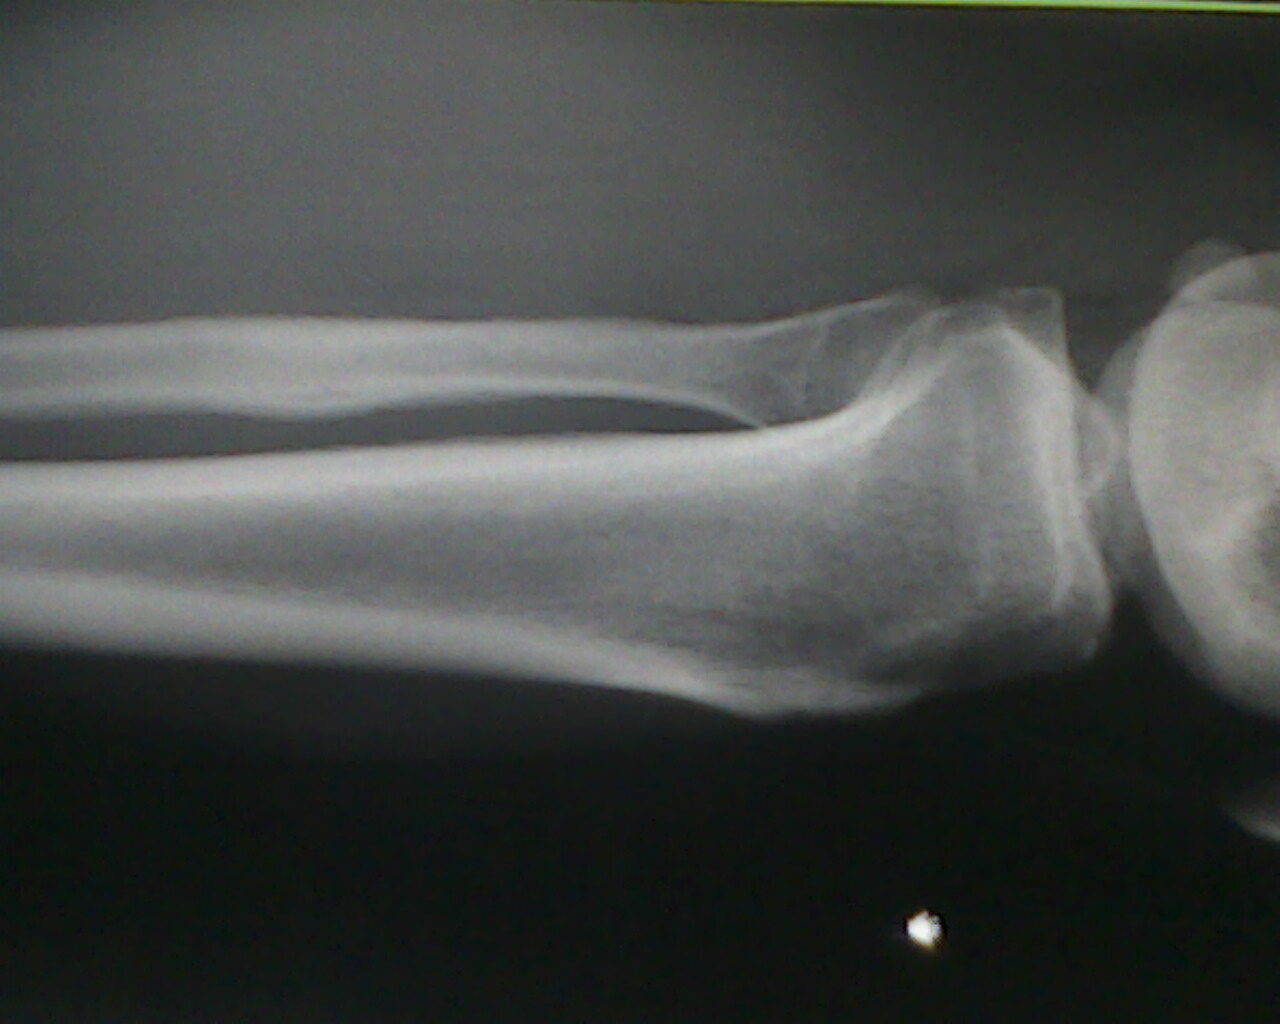

患者,男性  ,小腿肿胀。

不好意思。第二张翻了,大家讨论讨论腓骨病变

骨膜反应,软组织肿胀,未见骨质吸收破坏征象,当心骨肉瘤。建议ct检查

腓骨局限性梭形肿胀,支持首先往骨痂放向考虑,其他也不除外,随诊

首先可以肯定是个良性,疲劳性骨折(问病史,当兵的,长跑的,体育队的),陈旧性骨折(此前外伤没引起注意).

腓骨骨膜反应,骨质未见明显破坏,软组织肿胀。建议随访观察。